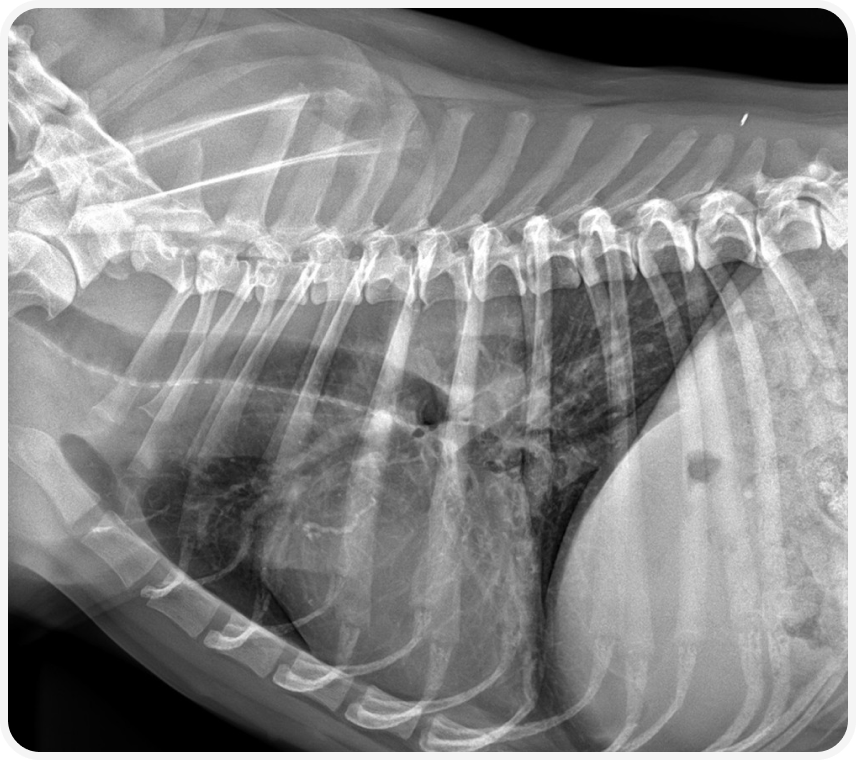

Общее состояние собаки было удовлетворительным, хрипов, лихорадки не было. На рентгенограмме визуализировался бронхиальный рисунок с бронхоэктазами и образованием мягкотканной плотности в области бифуркации.

Проведена КТ грудной клетки с контрастом: в дорсокаудальной части краниальной доли правого легкого определяется объемное образование с умеренным и равномерным накоплением контрастного препарата, размер 42*34*53 мм. Образование плотно прилегает к бифуркационному и правому трахеобронхиальному лимфатическим узлам, границы между образованием и ЛУ плохо определяются.